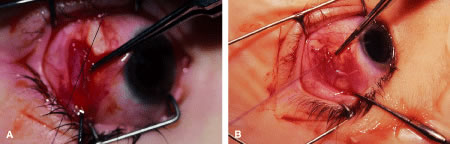

RECESSION PROCEDURE: FORNIX INCISION

This procedure is recession of the right medial rectus muscle. The eyelids are separated with a Barraquer open-blade wire eyelid speculum (Fig. 8). The open-blade design provides more room for exposure and makes it easier to pass the suture needles, especially in small children or when large recessions are performed. The globe is grasped with a Lester forceps at the limbus. It is best to grasp the limbus with the forceps held perpendicular to the globe and then to position the forceps so that they are rotated and lie tangential to the globe. Forced ductions are performed to detect any restriction of movement of the globe (Fig. 9).

|

The globe then is gently elevated from the orbit or proptosed at the same time it is abducted or adducted to prepare for the incision. Elevation of the globe helps to separate the horizontal rectus muscle from the inferior rectus muscle so that the inferior rectus muscle is not cut when the incisions are made. The conjunctiva is grasped by the assistant with a Manhattan toothed forceps (Fig. 10). This forceps has teeth that are angled outward and are designed to grasp conjunctiva, as well as the deeper subconjunctival tissue, so that when the blunt-tipped Westcott scissors cuts into the tented tissue, an incision is made into the conjunctiva and Tenon's capsule (Fig. 11A and B). If the incision does not completely penetrate Tenon's capsule and the intermuscular septum to the scleral surface of the eye, additional tissue (anterior Tenon's tissue and/or intermuscular septum) is grasped with the Manhattan forceps and at least one additional cut is made.